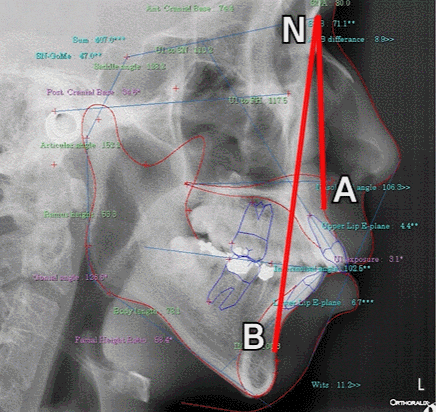

| * How is a receded chin diagnosed? An X-ray is used to measure the angle between the upper jaw and lower jaw (the ANB difference angle). The larger this angle is, the more it indicates that the lower jaw is skeletally positioned backward compared with the upper jaw. |